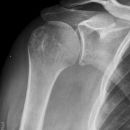

Knöcherner Supraspinatussehnenausriss